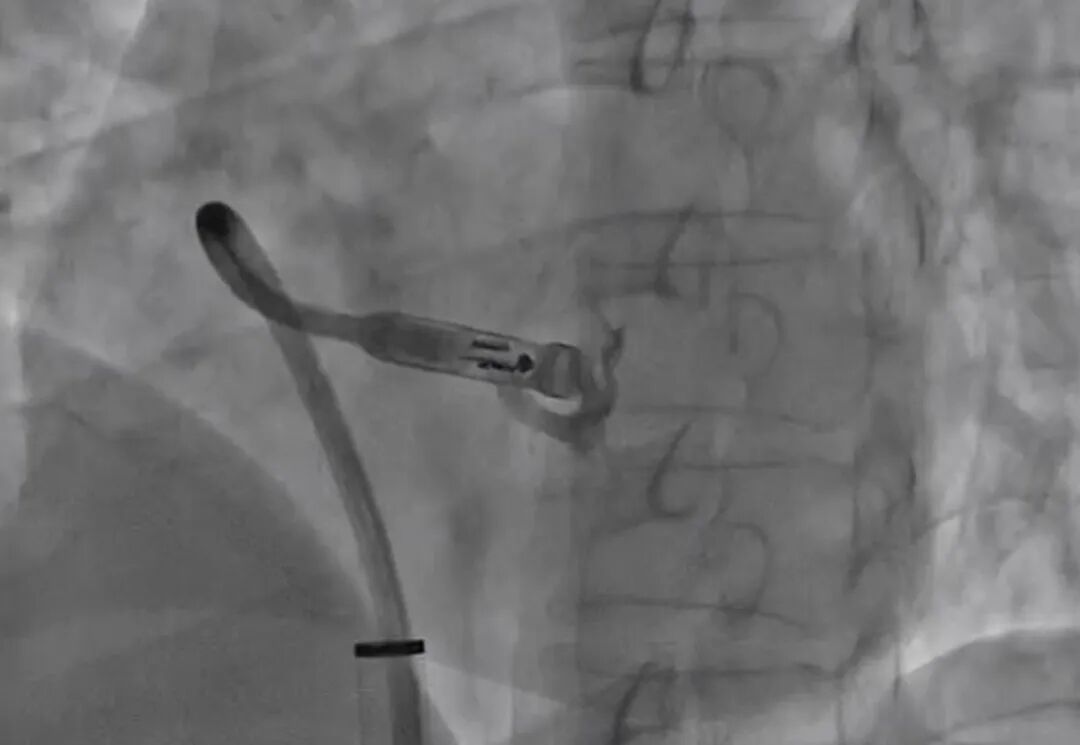

手术团队在超声和DSA的双重精准引导下,将装载着Micra无导线起搏器的输送系统沿血管缓缓送入心脏。它无需导线和皮下脉冲发生器,术后患者不仅可以正常洗澡、运动,还能安全接受核磁共振检查,彻底打破了传统起搏器的使用限制。

推送、调整、释放,每一步都要精准到0.1毫米。陈珂副主任介绍,手术团队凭借丰富的介入经验,操控着输送系统在血管中导航,最终将起搏器稳稳固定在李先生的右心室间隔部。经过现场测试,起搏器感知灵敏、起搏功能正常,原本紊乱的心脏节律瞬间恢复平稳。